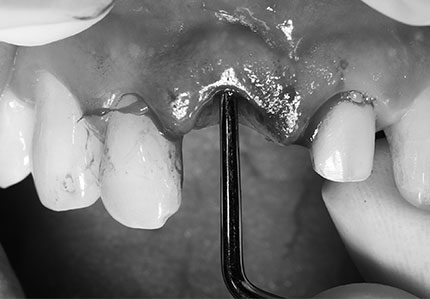

발치 후 비어있는 공간에 임플란트를 식립하였고,

추후 잇몸이 꺼져 보이지 않도록

부족한 부분에는 뼈이식을 추가로 진행하였어요.

저희 치과에서 사용하는 뼈이식 재료는

자연골과 뛰어난 상호작용과 높은 성공률을

보이는 과학적으로 안정성이 입증

스위스 잇몸뼈 이식재를 사용하고 있어요.

또한 골유착이 우수한 초신수성

임플란트도 함께 사용하고 있는데요❗

현존 표면 기술 중 골 유착 성능이

뛰어난 임플란트를 사용하여

감염 확률은 낮추고 혈액의 흡수성은

높일 수 있다는 장점이 있어요.

이로 인해 환자분의 경우처럼 뼈이식이

함께 진행되는 경우 더 우수한 골 유착을

기대해볼 수 있답니다.👍

임플란트를 식립하고 지혈한 후,

임시치아까지 들어간 모습이에요.👏